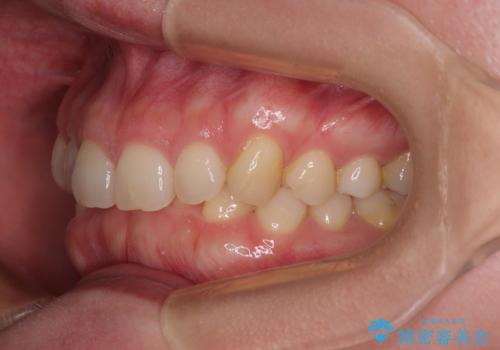

- 下顎前歯が完全に隠れてしまっていることを気にして来院された患者様です。

下顎の臼歯が手前に傾斜していることで咬み合わせが深くなってしまい、下顎前歯が見えないほどに上顎前歯が覆い被さっている状態でした。

下顎臼歯を起き上がらせるためにユーティリティーアーチを使用し、一気に深い咬み合わせを改善することができました。